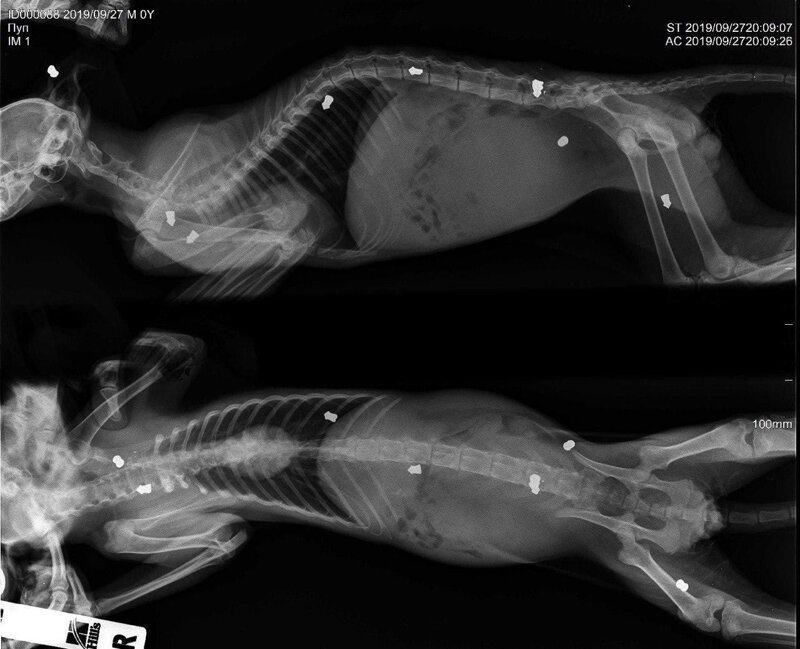

В Перми удалось спасти котенка, в которого 9 раз выстрелили из травматического пистолета и сломали позвоночник. Пушистик почти умер, а его задние лапки парализовало, но медикам удалось провести серьезную операцию и спасти его. Несмотря на такие серьезные травмы, ветеринары дают положительные прогнозы.